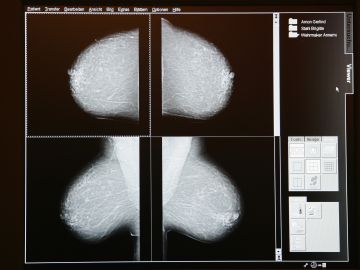

Imágenes digitales de un estudio de mamografía, técnica usada para detectar cáncer de mama. Crédito: Getty Images